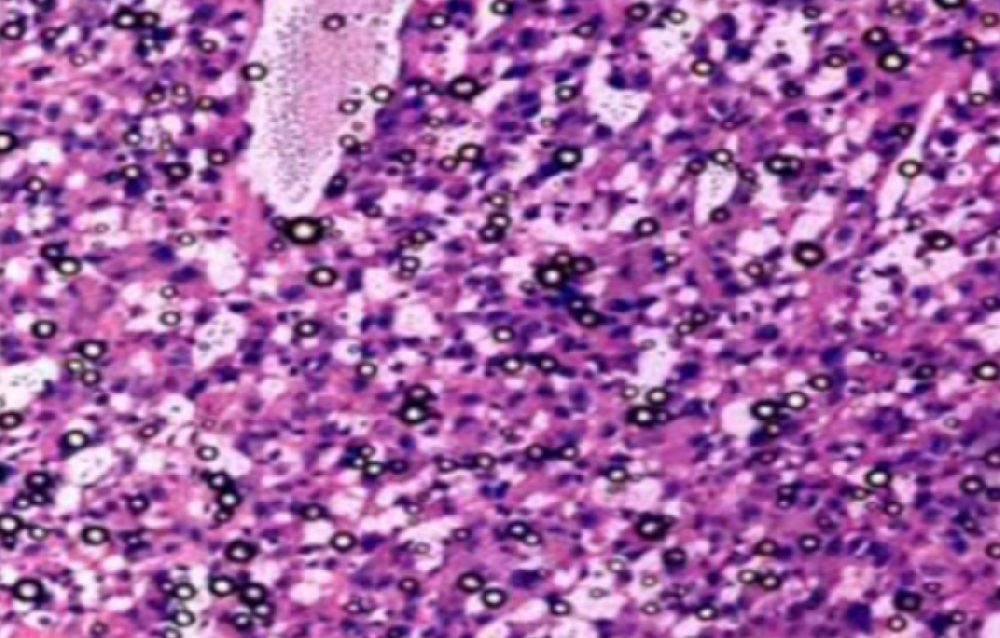

什么是粒细胞?什么是中性粒细胞、嗜酸性粒细胞、嗜碱性粒细胞、肥大细胞?